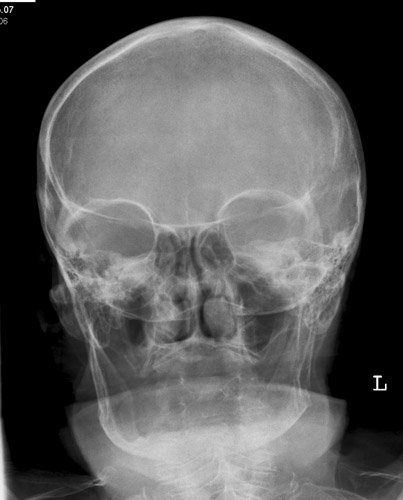

NNH p.a.

Fehler

Projektion der Felsenbeine in die diagnostisch wichtigen unteren Abschnitte der Kieferhöhle, in welchen sich bei einer frischen Sinusitis der Erguss ansammelt (auf der Aufnahme bei sitzendem Patienten!)

Abhilfe

Nasenspitze geringfügig vom Film abheben lassen, mit anderen Worten Kinn mehr vorstrecken; Kopf mehr nach hinten nehmen.